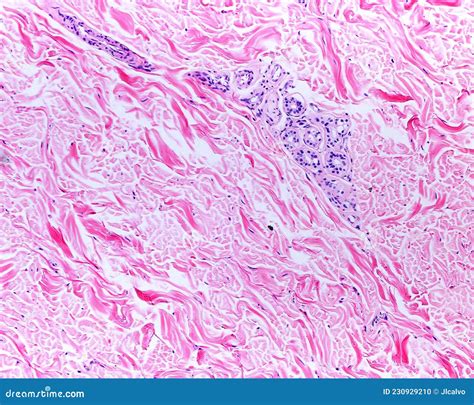

Dense Irregular Ct Scan Image

• dense irregular connective tissue

• dense irregular ct found where

• dense irregular function and location

• dense irregular ct location